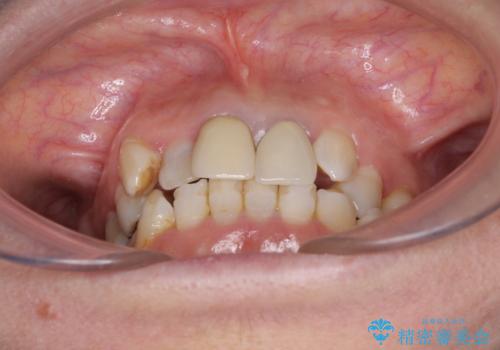

奥歯の銀歯は、セラミッククラウンを装着するには歯の高さが不十分であり、そのままでは矯正治療を行うことが困難であるため、歯冠長延長術を行うこととしました。

外科処置に対する恐怖心が強かったため、処置の際には静脈内鎮静法を用いて、リラックスした状態で行いました。

歯冠長延長術を行ったことで、自然な形態かつ清掃性の高いセラミッククラウンを装着することができました。